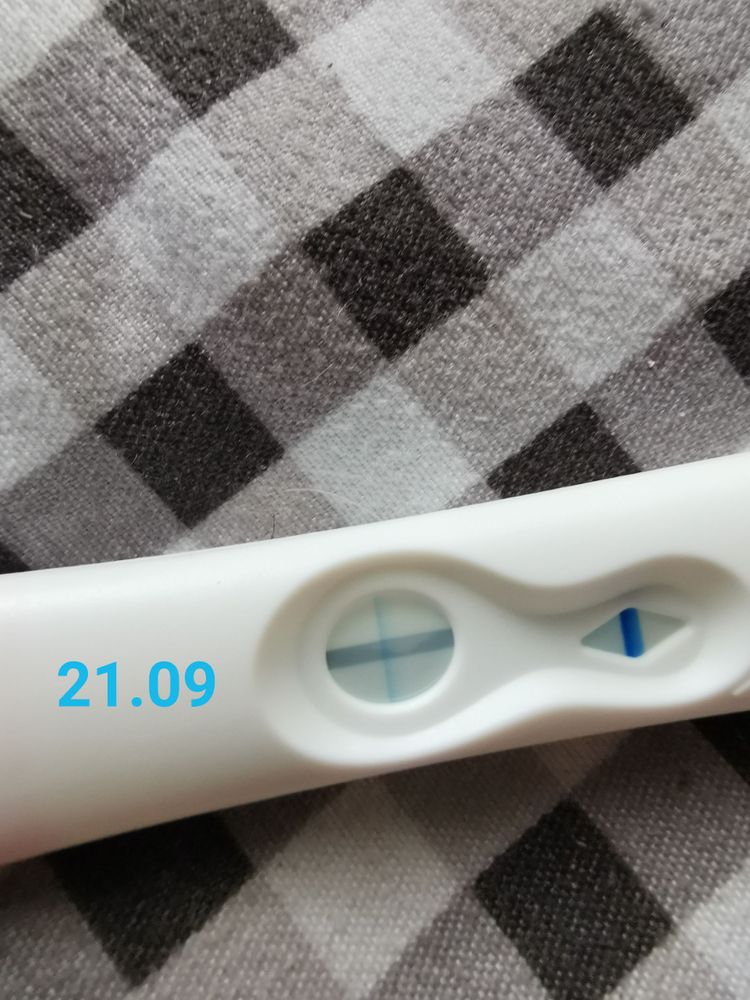

🌿15 тестов на беременность 🤦♀️🙆♀️